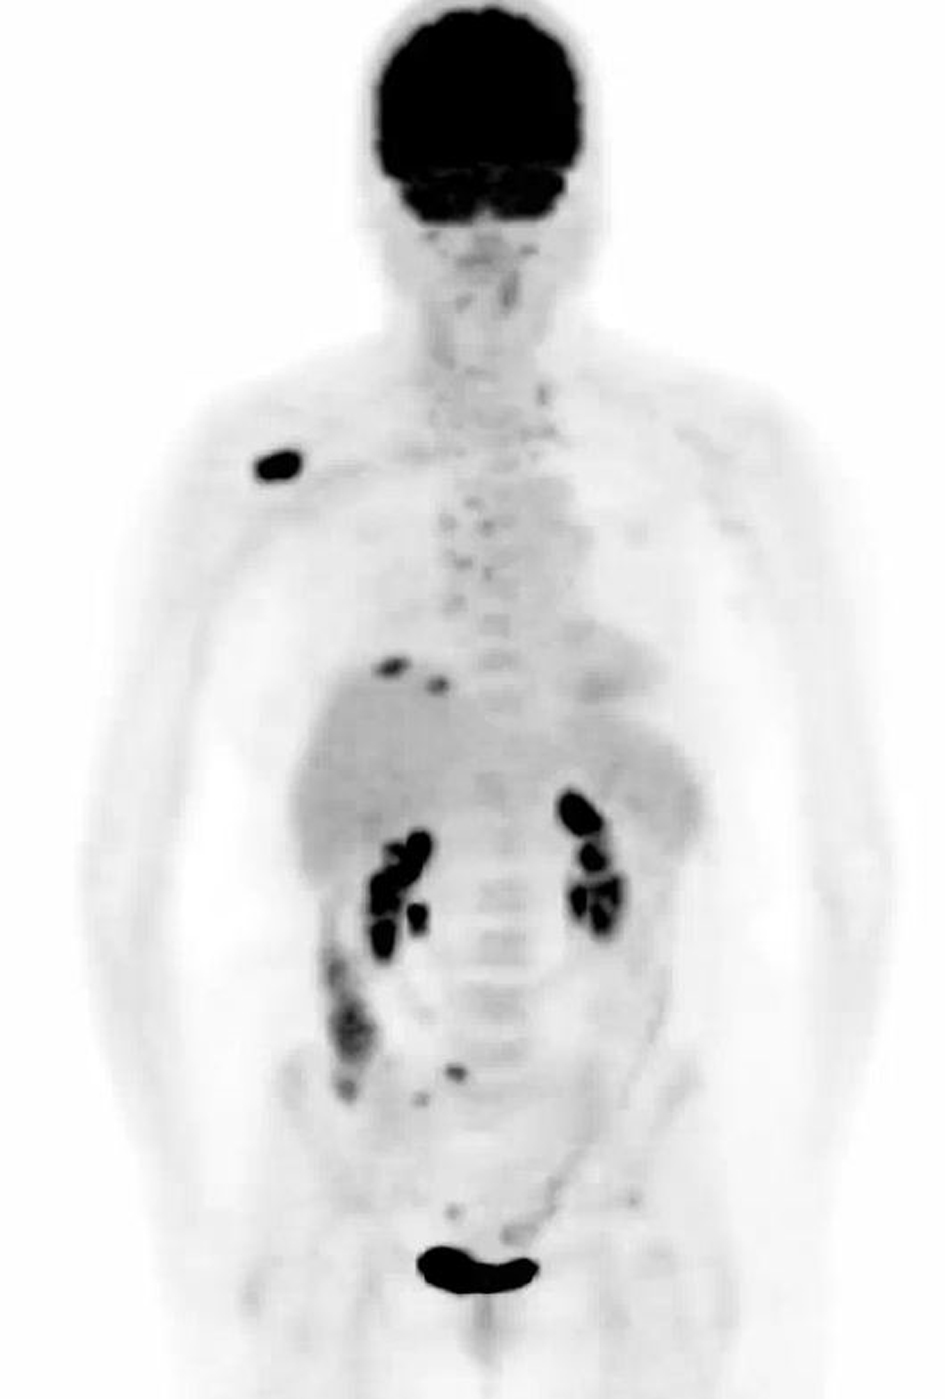

A CT-positron emission tomography (PET) scan (Fig. 1) showed a 2.3-cm mass in the anterior right lung showing increased metabolic activity with a standardized uptake value (SUV) of 3.8. Multiple metabolically active lymph nodes were located in the mediastinum, left supraclavicular region and retroperitoneum. Multiple bone metastases were detected in the ribs, sacrum and the right scapula. A right scapular lesion had an SUV of 10.6. Magnetic resonance imaging (MRI) of the brain did not show any evidence of parenchymal or leptomeningeal metastatic disease.

![]() Click for large image | Figure 1. Computed tomography-positron emission tomography performed prior to treatment. Maximum intensity projection image shows mass within right lung base. Adenopathy with abnormal uptake is present throughout the mediastinum and neck. Largest bone metastasis involves right scapula. |